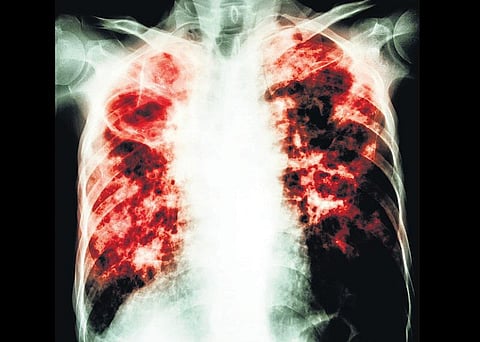

டி.பி. எனப்படும் காசநோய்தான். மிகச் சுலபமாகப் பரவும் ஆபத்து கொண்ட இந்த நோய், பாதிக்கப்பட்டவர்களை உருக்குலைத்துவிடக்கூடியது.

டியூபர்செல் பாசிலஸ் அல்லது டியூபர் குளோசிஸ் என்பதன் சுருக்கம்தான் டி.பி.. பாதிக்கப்பட்டவர் இருமும்போதும், சளியை வெளியில் துப்புவதன் மூலமே மற்றவர்களுக்குக் காற்று மூலம் இந்த நோய் பரவுகிறது. வீட்டில் காசநோயாளி இருந்தால் இந்த நோய் குழந்தைகளுக்கு எளிதில் பரவிவிடுகிறது. நோய் எதிர்ப்புச் சக்தி குறைவாக இருப்பவர்களுக்குக் காசநோய் எளிதில் தொற்றிக் கொள்ளலாம்.

பொதுவாக ஒருவருக்குக் காசநோய் இருக்கிறதா என்பதை எப்படி அறிவது? தொடர்ந்து இருமல், சளியுடன் ரத்தம் வருவது, காய்ச்சல், இரவில் குளிர் நடுக்கம், நெஞ்சில் வலி, இரவில் அதிகம் வியர்ப்பது ஆகியவை இந்த நோய்க்கான அறிகுறிகள். இந்த அறிகுறிகள் உள்ளவர்களுக்கு காசநோய் இருக்கிறதா என்பதைச் சளியை எடுத்துப் பரிசோதிப்பதன் மூலம் உறுதிப்படுத்தலாம்.

காசநோயை ஆரம்ப நிலையிலேயே கண்டுபிடிப்பது மிகவும் முக்கியம். அப்படிக் கண்டுபிடித்துவிட்டால் ஆறு மாதங்களில் மருந்து, மாத்திரைகள் சாப்பிட்டு நோயைக் குணப்படுத்திவிடலாம். காசநோயில் மரணம் ஏற்படுத்துவது ‘மல்டி டிரக் ரெசிஸ்டன்ஸ்’ (எம்.டி.ஆர்.-டி.பி.) என்ற நிலையில்தான்.

காசநோய் வந்து சரியாக மருந்து மாத்திரைகள் சாப்பிடாமல் இருப்பது, முறையான சிகிச்சை எடுத்துக் கொள்ளாதது போன்ற காரணங்களால் இந்த நிலைக்குச் செல்பவர்கள் உண்டு. இந்த நிலைக்கு வருபவர்கள்தான் மரணத்தைத் தழுவ நேரிடுகிறது.